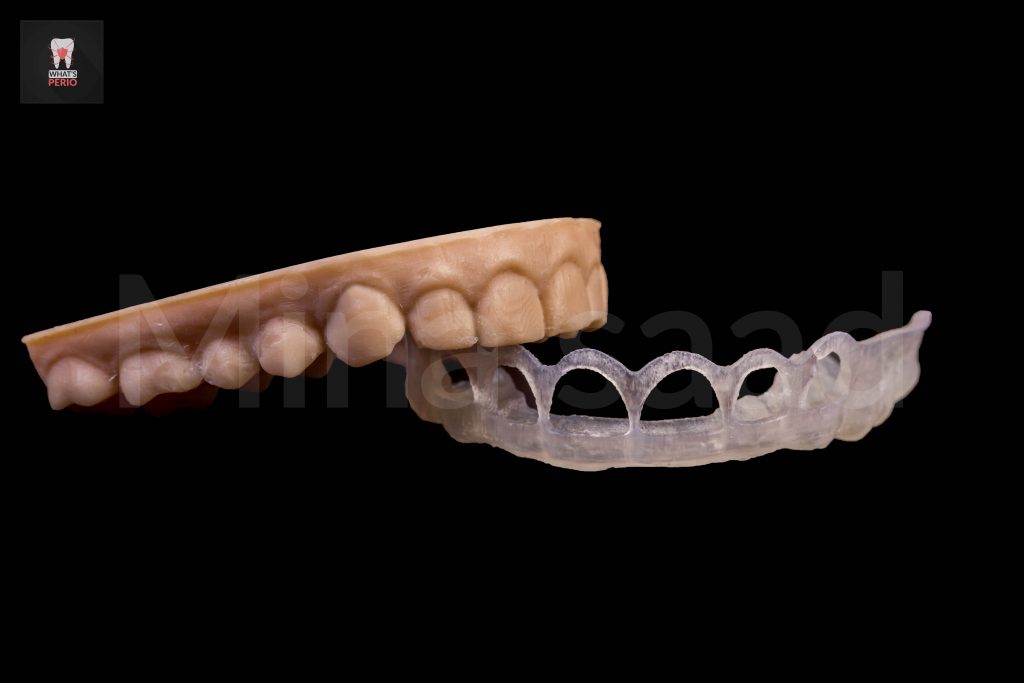

-Soft tissue scan image & CBCT image were merged together to design a Digital crown lengthening guide.

-The digital guide has 2 level:

1-Coronal level: which is determined upon probing depths on the whole upper anterior quadrant.

2-Apical level: which is determined upon CBCT to accurately determine the needed sufficient biologic space for supracrestal fibers. “2mm”

-The guide was printed & was tried over a 3d model & also intraorally to check the coronal level is exactly like the pobing depths which were taken.